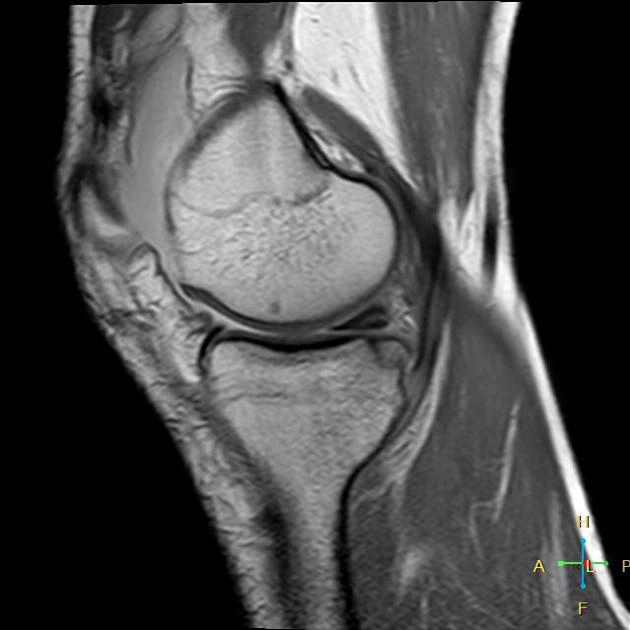

• Gãy bong khớp gối

Gãy bong điểm bám dây chằng chéo trước (Anterior cruciate ligament avulsion fracture- ACL)